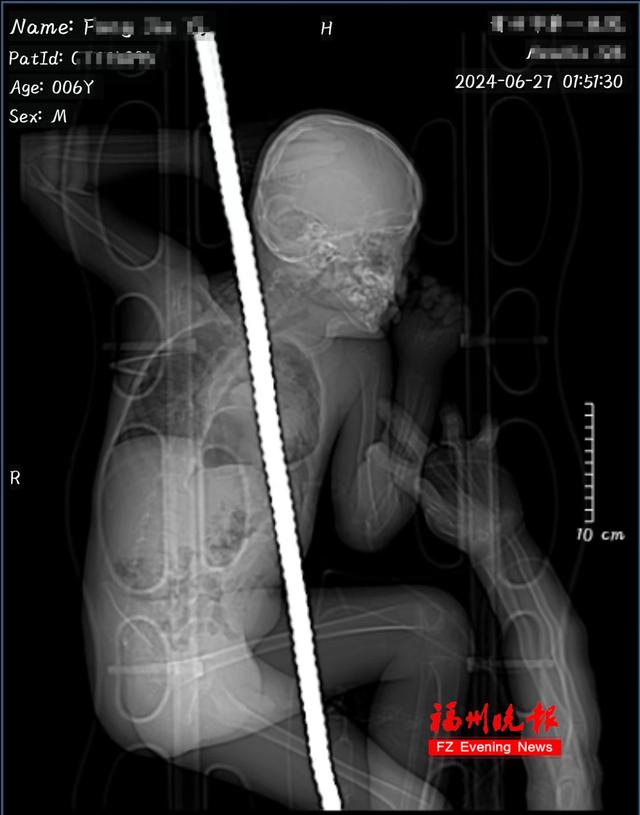

被一根一米多长、锈迹斑斑的钢筋

斜向贯穿了腹部、胸腔和肩部

男孩侧躺在病床上,比手指还粗的钢筋穿透出腹部和肩部,露出狰狞的两端。

“那根钢筋,从左上腹插入,造成胃被捅了前后两个大口,大肠和小肠有不同程度撕裂,左肝有一个裂口并疝入胸腔,左肺也有破裂出血。

同时,钢筋还紧贴着心脏后方和左肺血管,最后从左颈肩部穿出。此外,他的胸腹腔内还残留着大量血性积液及铁锈。”